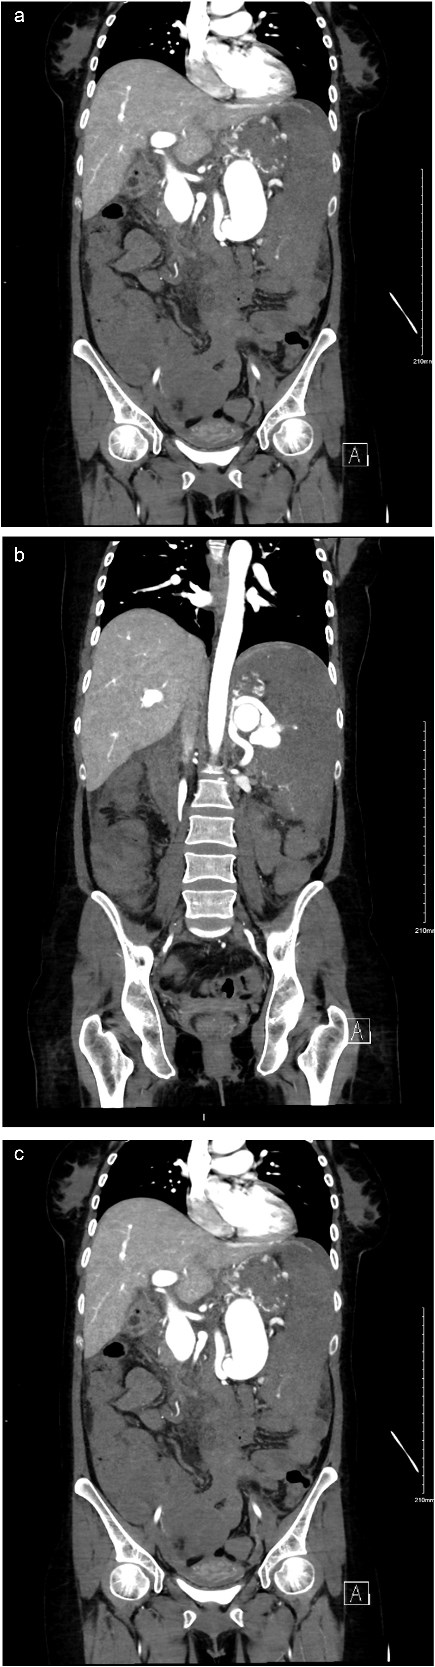

A computed tomography (CT) scan was obtained as part of the patient’s investigation plan, for which it revealed: no active bleeding. There was a distal SAA measuring 1.9 cm (Fig. 1c) with focal arteriovenous (AV) fistula with the distal splenic vein causing shunting of the flow with resultant severe aneurysmal dilatation of the splenic vein measures 3.4 × 9 × 4 cm (Fig. 1a–c). There were signs of portal hypertension seen as dilated portal vein measuring 2.8 cm (Fig. 2a and b) enlarged spleen measuring 20 cm. Other than that, the remaining of the CT was unremarkable.

(a) Coronal view of enhanced CT of abdomen and pelvis showing dilated splenic vein lateral to the artery. (b) Coronal view of enhanced CT of abdomen and pelvis showing dilated splenic vein causing portal hypertension. (c) Coronal view of enhanced CT of abdomen and pelvis delayed imaging showing the AV fistula at the hilum.